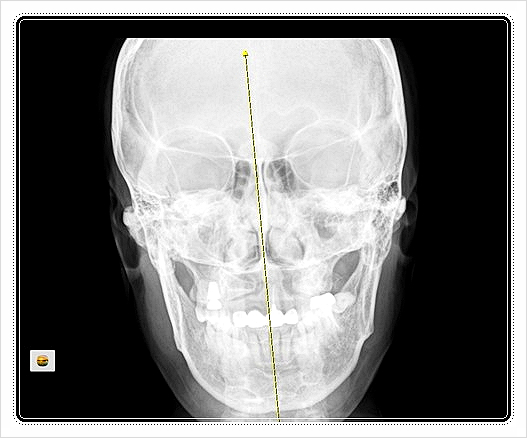

경추 2번은 머리를 회전시키는 핵심 축입니다.

이 축이 조금만 틀어져도, 거울에서 보는 얼굴 중심선이 달라 보이죠.

그 결과 턱이 한쪽으로 밀리거나 광대 한쪽이 도드라져 보일 수 있습니다.

즉, 얼굴 비대칭의 증상은 얼굴에서 나타나지만 원인은 목에서 비롯되는 경우가 많습니다.

그래서 안면 교정 시 경추까지 함께 보는 것이 자연스러운 접근입니다.